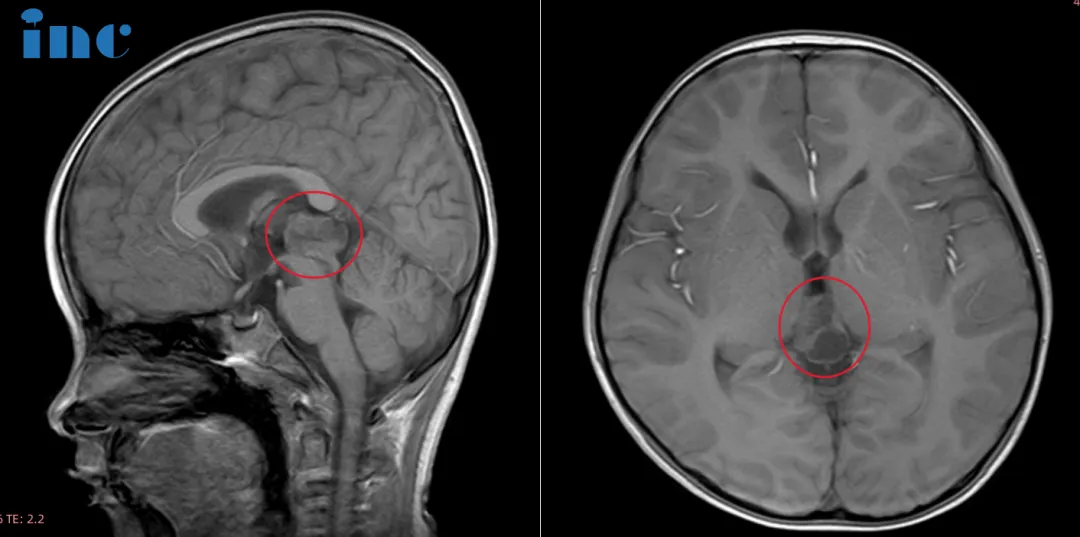

六岁的鑫鑫,因在幼儿园意外摔伤头皮就诊,CT检查意外捕捉到松果体区阴影与局部钙化灶;进一步MRI精查,一枚221417mm的占位病变随之浮出水面。 三十六岁的晴晴,不过是因鼻炎顺带行颅脑...